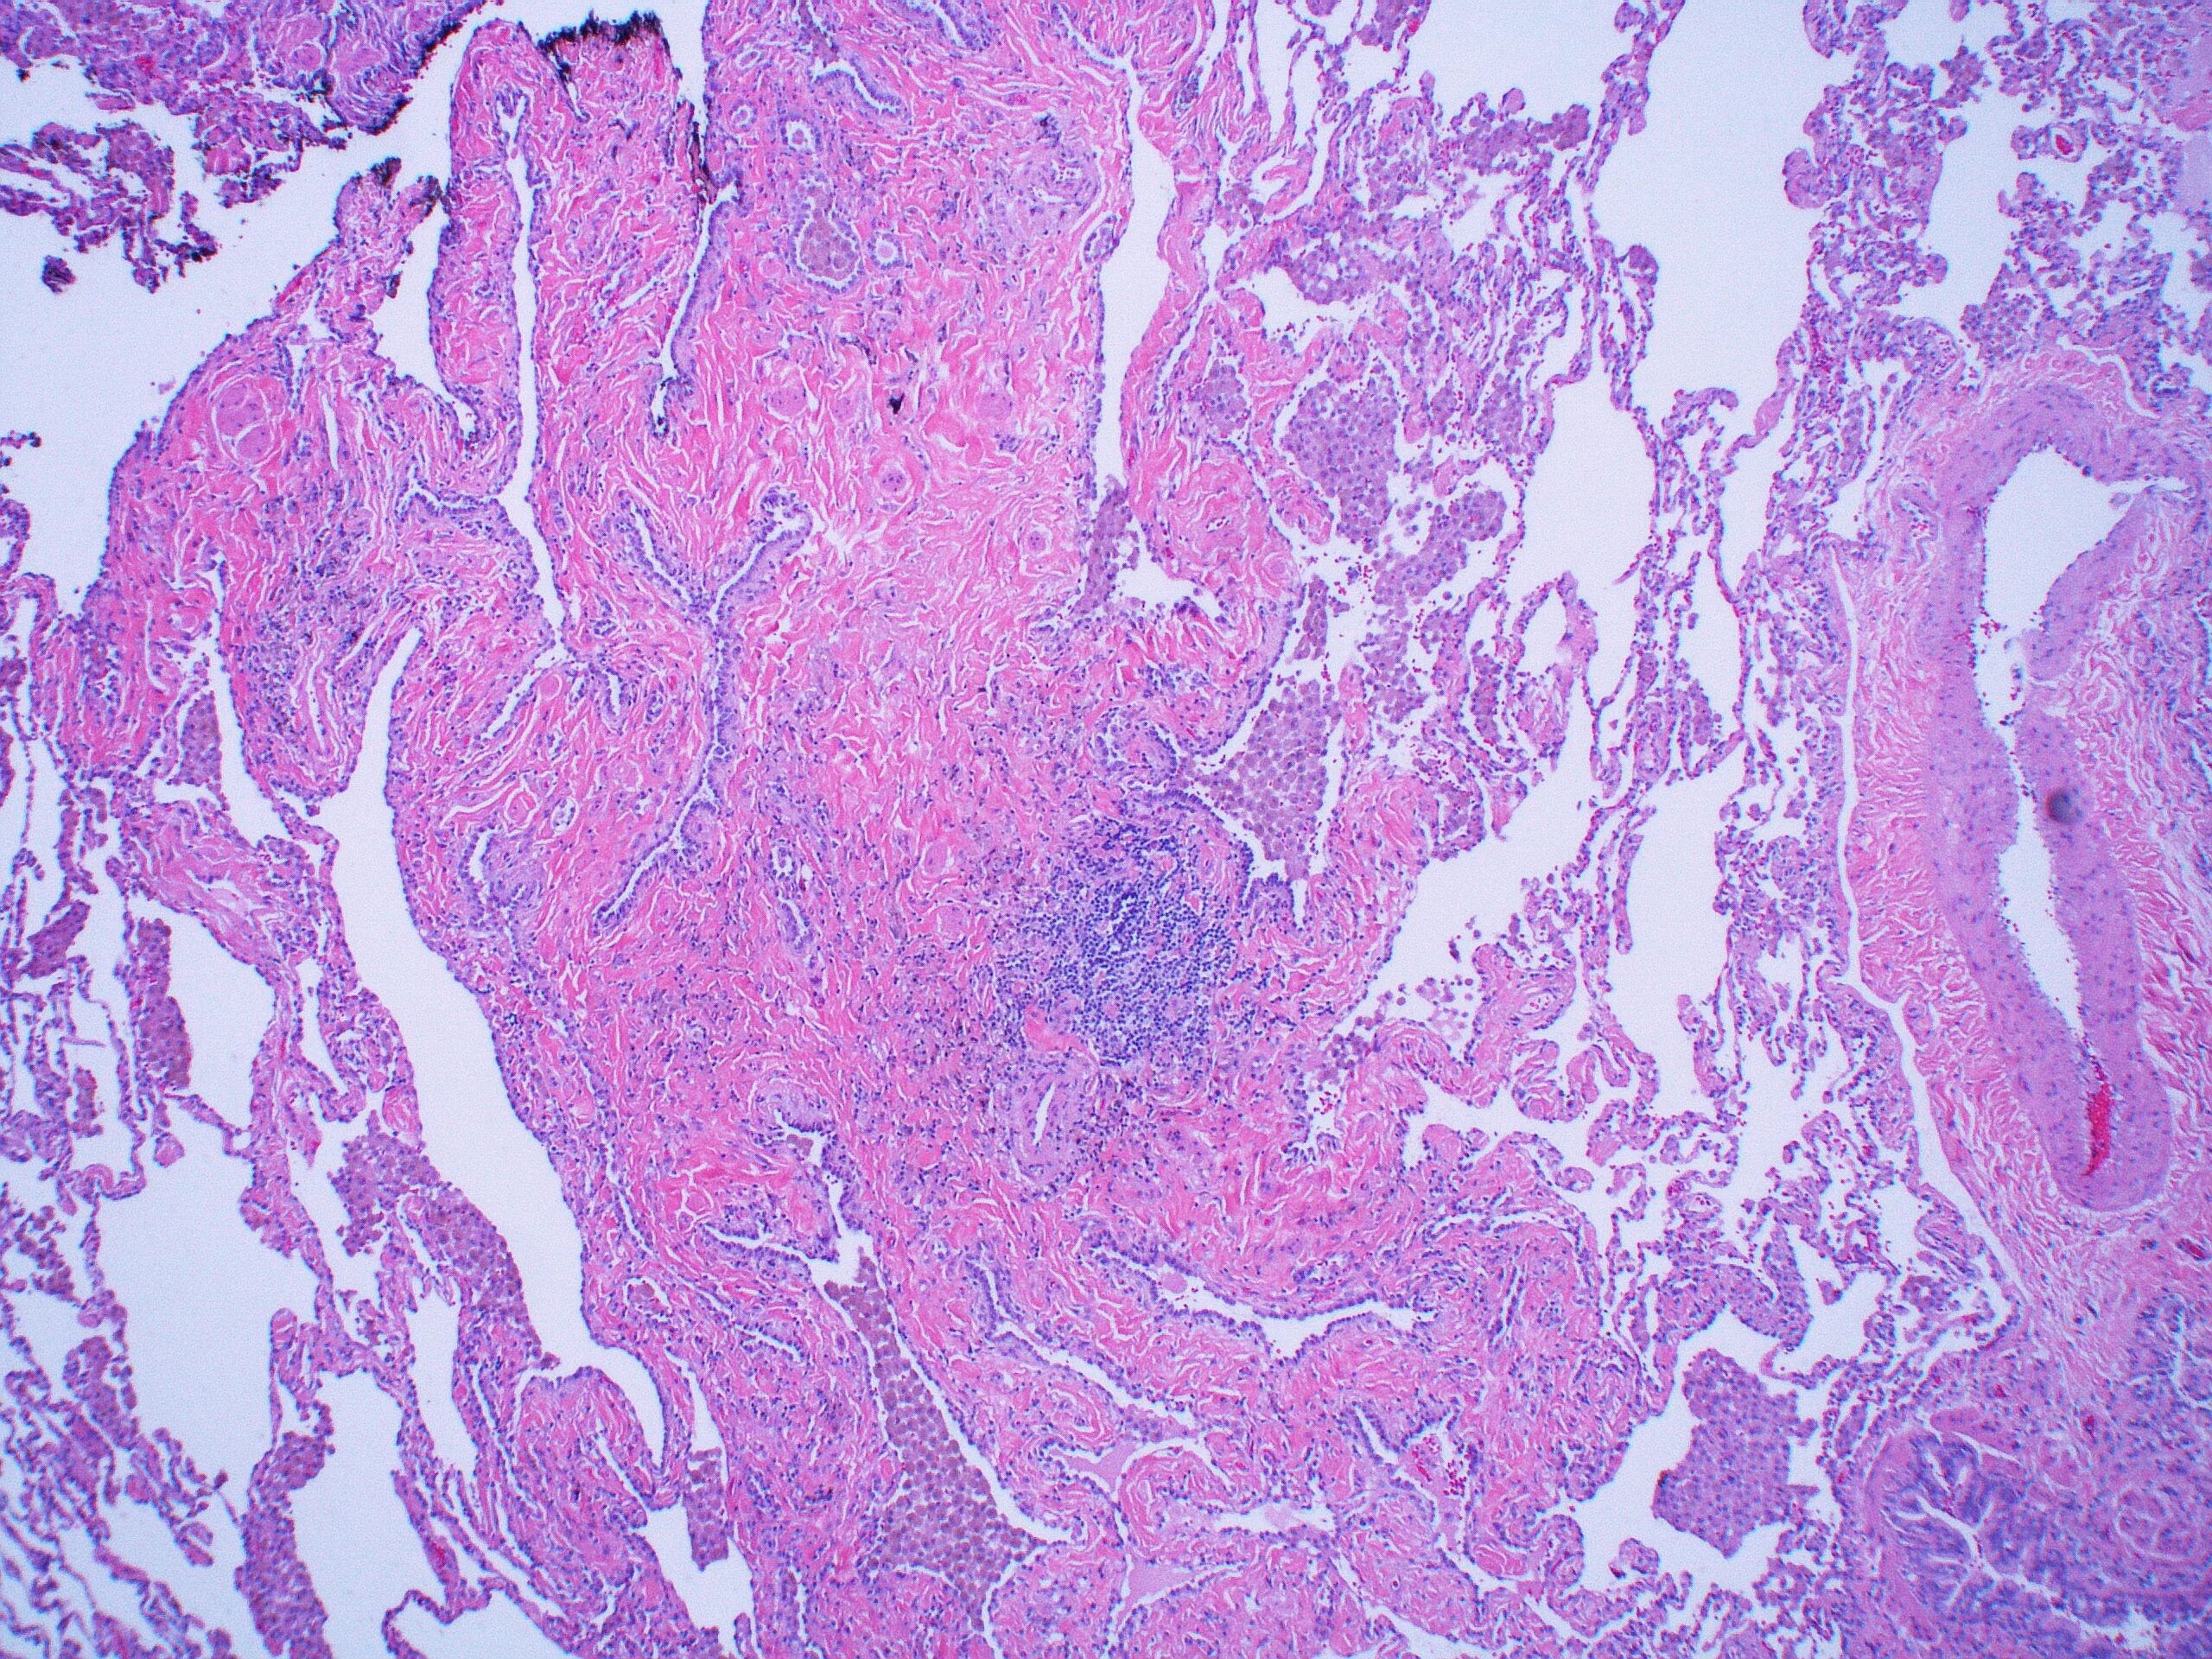

Синусовый гистиоцитоз лимфатического узла